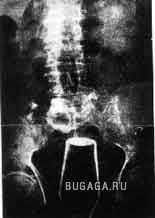

Ни для кого теперь уже не секрет, что у людей есть жопы. У каждого она своя и у всех разные. Жопы бывают человеческие и другие, большие и маленькие, плоские и выпуклые, висячие и упругие, в общем, всякие. А еще жопы бывают сытые и голодные. У кого сытая попа, тот её холит и лелеет, она вся такая ранимая и нежная. А у кого голодная жопа, тот её пичкает всем, что попадётся под руку, может затолкать туда всё, что угодно. Такую жопу ничто не берёт. Ни слово, ни дело, ни заноза, ни пуля, ни штык, ни добрый подсрачник! Прозвали их люди чудо-жопы! Чудо-жопы имеет не каждый, а только тот, кто регулярно упражняется в скармливании жопе различных инородных предметов. Этих ректальных сластолюбцев люди тоже кое-как прозвали, но мы не будем отвлекаться, с нас достаточно знать факт, что люди имеют жопы. Кто воспламенел желанием поэкспериментировать, но не знает, что именно засунуть в недра своего драгоценного проголодавшегося зверя, предлагаю посмотреть варианты. Ну а кому просто интересно, тот глазеет на серию снимков, сделанных медиками в разное время и в разных странах, но в одинаково патологичных случаях. Можно также прочитать пару случаев кормления, и чем это закончилось. Кого картинки могут задеть за живое, не принимайте близко к… живому :):):)

Список вещей, извлеченных из чудо-жоп:)

Разные предметы:

Стакан и чашки -12